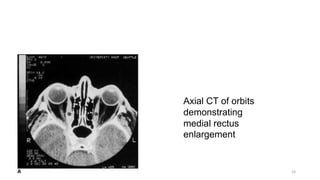

Axial CT of orbits

demonstrating

medial rectus

enlargement